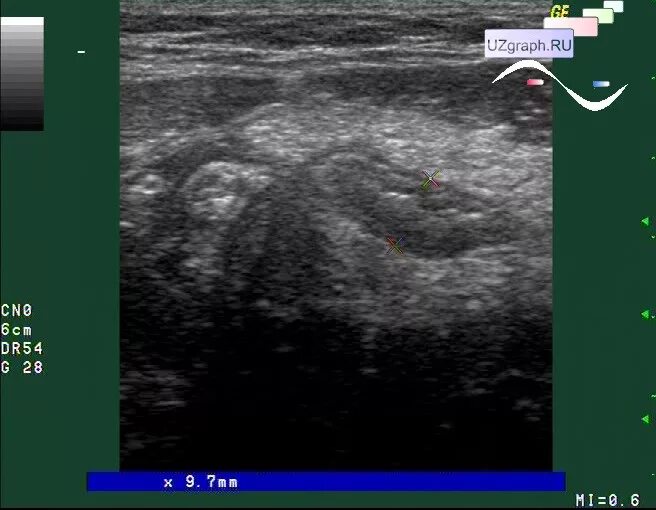

Аппендицит на узи можно ли